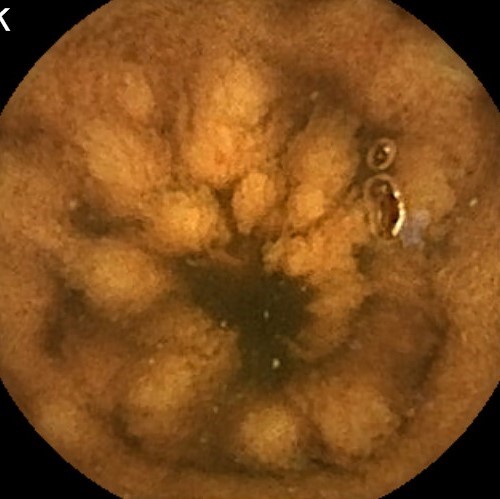

Capsule Endoscopy: Ileum Terminale, Lymphoid Hyperplasia

Capsule Endoscopy: Ileum Terminale, Lymphoid Hyperplasia. Just click on a picture!